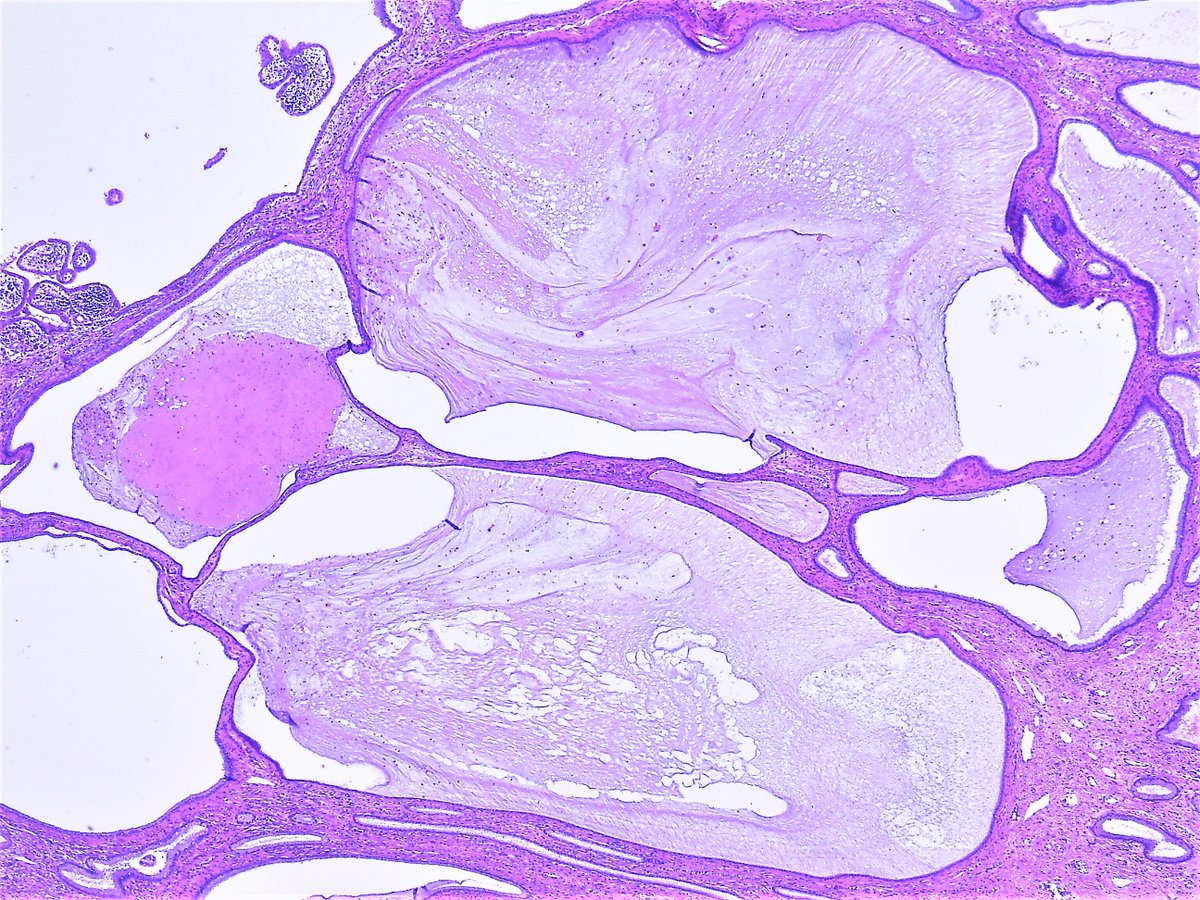

Nabothian cysts also called mucinous retention cysts or epithelial cysts are a common and benign gynecological condition located at the uterine cervix. They are usually asymptomatic of no clinical significance and require no treatment. However if symptomatic or they become complicated further evaluation and therapy are needed.

Pathology Outlines - Nabothian cyst Colloid cysts of the third ventricle are benign epithelial lined cysts with characteristic imaging featuresAlthough usually asymptomatic they can rarely present with acute and profound hydrocephalus. It is a specific type of giant cell in which several epithelioid meaning the cells are big and pink like the cells of the skin macrophages fuse together the nuclei forming a cute horse-shoe shape around the periphery of the cell The topic Cervical Mucinous Retention Cyst you are seeking is a synonym or alternative name or is closely related to the medical condition Nabothian Cyst of Uterine Cervix. Nabothian cysts Squamous metaplasia grows over endocervical glands Mucin gets trapped in glands leading to cystic dilation Nabothian cyst Extremely common of no clinical significance.

Nabothian Cyst of Uterine Cervix is a benign mucus-filled cyst that is present on the cervical wall. It is common tumor found mostly in middle-aged and older women who have had multiple pregnancies. There are no clearly established risk factors for Nabothian Cyst of Uterine Cervix.